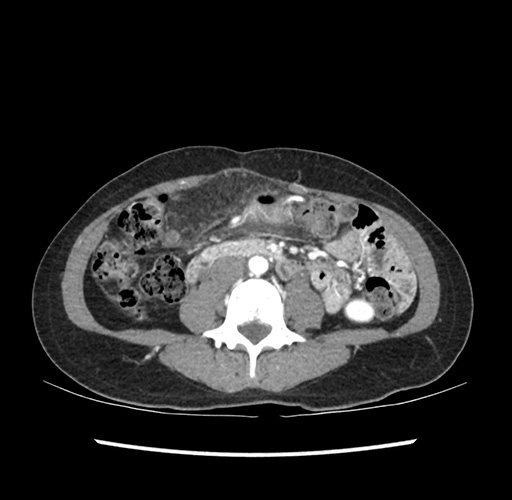

Imaging Analysis

Look through the patient's CT scan to identify any areas of concern for the necessary procedure.

Based on your CT findings, which issue(s) would give reason for "planned slowing down moment(s)" in this case?

Considering a standard left lateral sectionectomy procedure, what step(s) of the operation would you do differently in this case ?